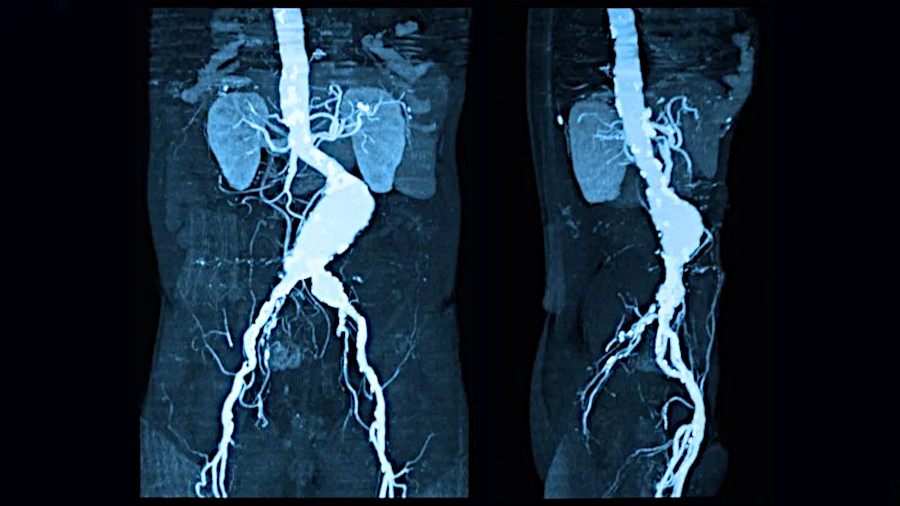

- Aneurisma dell'aorta

- Attivazione [!]: di svalutazione per la convinzione che il sangue non scorre bene o abbastanza velocemente.

- Foglietto embrionale: Mesoderma recente o dorsale.

- Fase: attiva in sospeso. Perdita cellulare recidivante nella parete arteriosa.

- Osservazione: Gli aneurismi si trovano solitamente nell'arteria addominale. Sono generalmente segmenti alterati da arteriosclerosi (indicazione di un attivazione presente da molto tempo). Gli aneurismi sono prodotti da un indebolimento della parete arteriosa. La rottura di un aneurisma è una EMERGENZA CHIRURGICA.